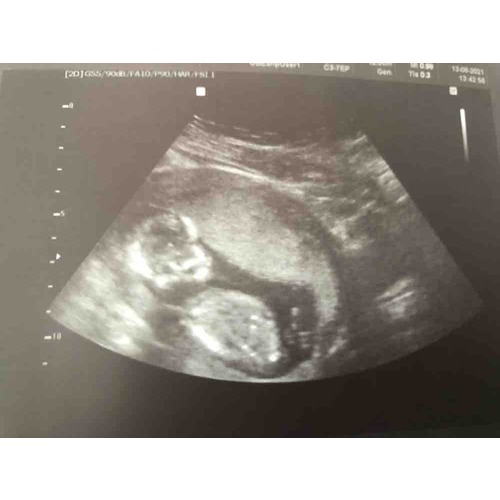

Leuke echo foto heb je trouwens, bijna dezelfde als ik!